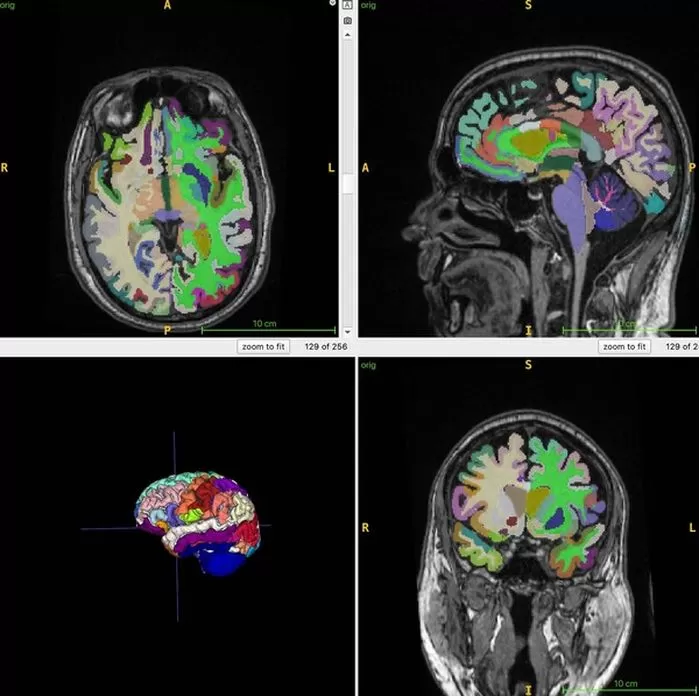

연구팀은 전신 MRI 촬영을 통해 참가자들의 근육과 지방 분포, 뇌 조직을 정밀 분석했으며, 인공지능 기술을 활용해 총근육량과 내장지방, 피하지방, 뇌 나이 간의 상관관계를 규명했습니다.

지방과 체액, 근육이 서로 다른 색으로 구분되는 특수 기법을 적용해 각 조직의 양을 정량화했으며, 뇌의 구조적 MRI 영상을 바탕으로 뇌 나이를 추정했습니다.